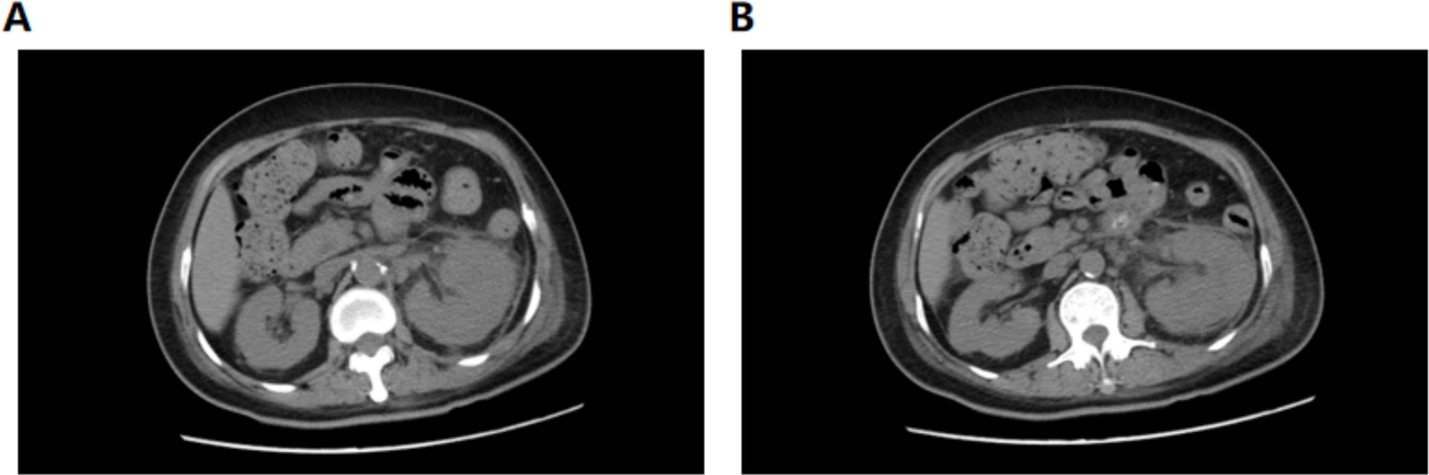

On postoperative day 10, renal ultrasound revealed localized renal sinus separation and minimal perirenal exudation in the left kidney. The patient demonstrated significant clinical improvement with marked reduction in fever peaks (Supplementary Figure S2), declining inflammatory markers (Figure 3), improved renal function, along with three consecutive days of drainage output consisting of pale yellow fluid. The drainage catheter was subsequently removed. Antimicrobial therapy was de-escalated from meropenem to cefoperazone-sulbactam (3 g, IVD, q8h). After 3 additional days of treatment with maintained apyrexia (body temperature consistently <37.2 °C) and satisfactory infection control, the patient was discharged with marked clinical improvement. The discharge instructions primarily comprised: (1) oral faropenem (0.2 g, PO, q8h) for antimicrobial therapy; (2) a scheduled follow-up outpatient visit in 2 week; and (3) strict monitoring and control of blood glucose levels. However, she was readmitted 1 day post-discharge with the return of symptoms including flank discomfort, fever (Tmax 38.5 °C) and episodic vomiting. She was investigated in the middle and lower abdominal scans: largely inflammatory changes in the left kidney and ureter (Figure 4), with hsCRP of 101.5 mg/L and leukocytes of 10.54 × 109/L. Cefoperazone-sulbactam was given to counteract the infection, and she was rechecked 1 week later with hs CRP of 45.1 mg/L and leukocytes of 9.29 × 109/L. The patient was successfully discharged on February 19. During the subsequent one-month follow-up period, she maintained no chills and fever, no nausea and vomiting, and no obvious back pain.